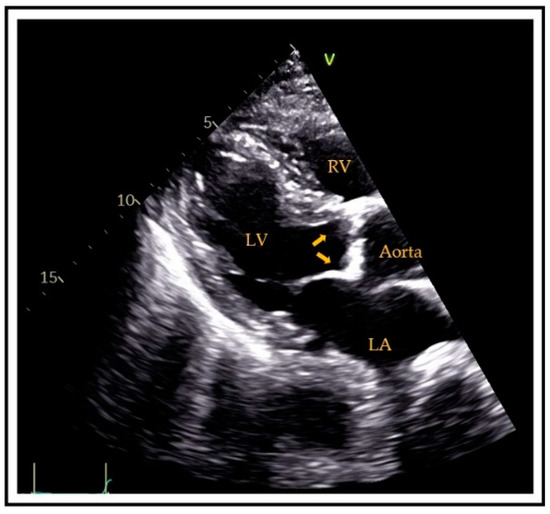

4.1. Ultrasound